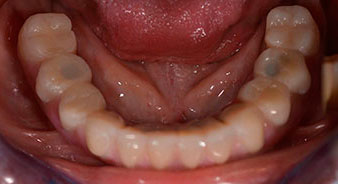

La paciente de 64 años se presentó con una dentición residual compuesta por las piezas dentales 38, 33 y 43 en el maxilar inferior y con una prótesis temporal fijada con ganchos en el maxilar inferior (figs. 1 y 2).

Para la planificación y la minimización del riesgo, se realizó una tomografía volumétrica tridimensional (TVD, Planmeca) que mostró que la calidad y la cantidad del tejido óseo era suficiente para la intervención quirúrgica y el tratamiento inmediato con el método Fast & Fixed. Siguiendo el protocolo de este método, se insertaron los implantes en la región de las piezas 35, 32, 42 y 45. Debido a la inclinación de hasta 45 grados de los implantes distales, el perfil de emergencia se desplazó hacia posterior y se generó un mayor polígono de soporte (fig. 3).